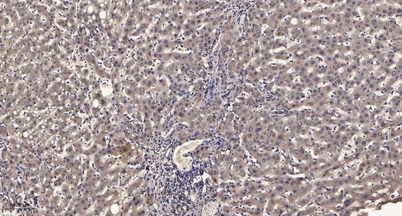

Immunohistochemical analysis of paraffin-embedded human liver cancer. 1, Antibody was diluted at 1:200(4 overnight). 2, Tris-EDTA,pH9.0 was used for antigen retrieval. 3,Secondary antibody was diluted at 1:200(room temperature, 45min).